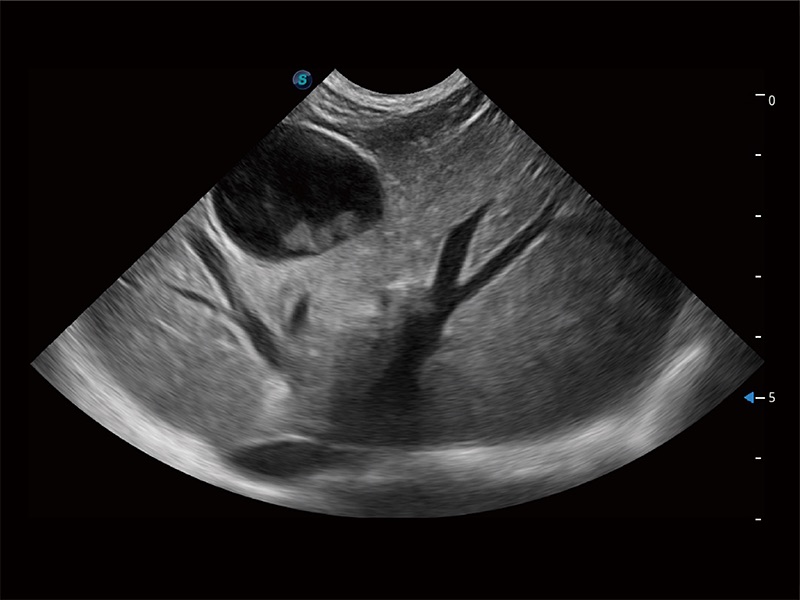

高性能和先进的临床应用工具可以为动物医生提供临床信心。ProPet 80 搭载了先进的腹部和浅表应用工具,帮助医生在日常临床实践中发挥前所未有的作用。

极大提升超低速微细血流的检出能力,同时更精准地滤除软组织和超声信号,为兽用医生提供以往无法通过常规血流获得的疾病诊断信息。